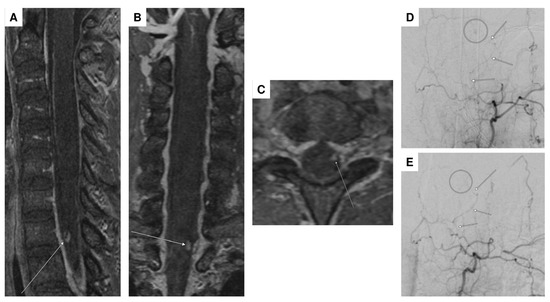

| 5 | F | 73 | headaches and pain in the back/neck pain | pronounced paraparesis of both legs | spinal SAH; angiographically, no evidence of an aneurysm | anticoagulation (rivaroxaban) | abdominal/thoracic CTA, multiple DSA, multiple spinal MRI | surgical procedure (evacuation of an intradural hematoma) |

| 6 | M | 55 | pain between the shoulder blades and the cervical spine, tingling sensations in all four extremities | tingling sensations in all extremities, unable to lift the legs, weakness in both arms | epidural bleeding and spinal SAH; suspected perimedullary aneurysm at T1/2; angiographically, no evidence of an aneurysm, epidural bleeding may be due to a microspur at T1/2 | microspur | multiple DSA, multiple spinal MRI | surgical procedure (evacuation of an epidural hematoma), then conservative (no evidence of an aneurysm) |